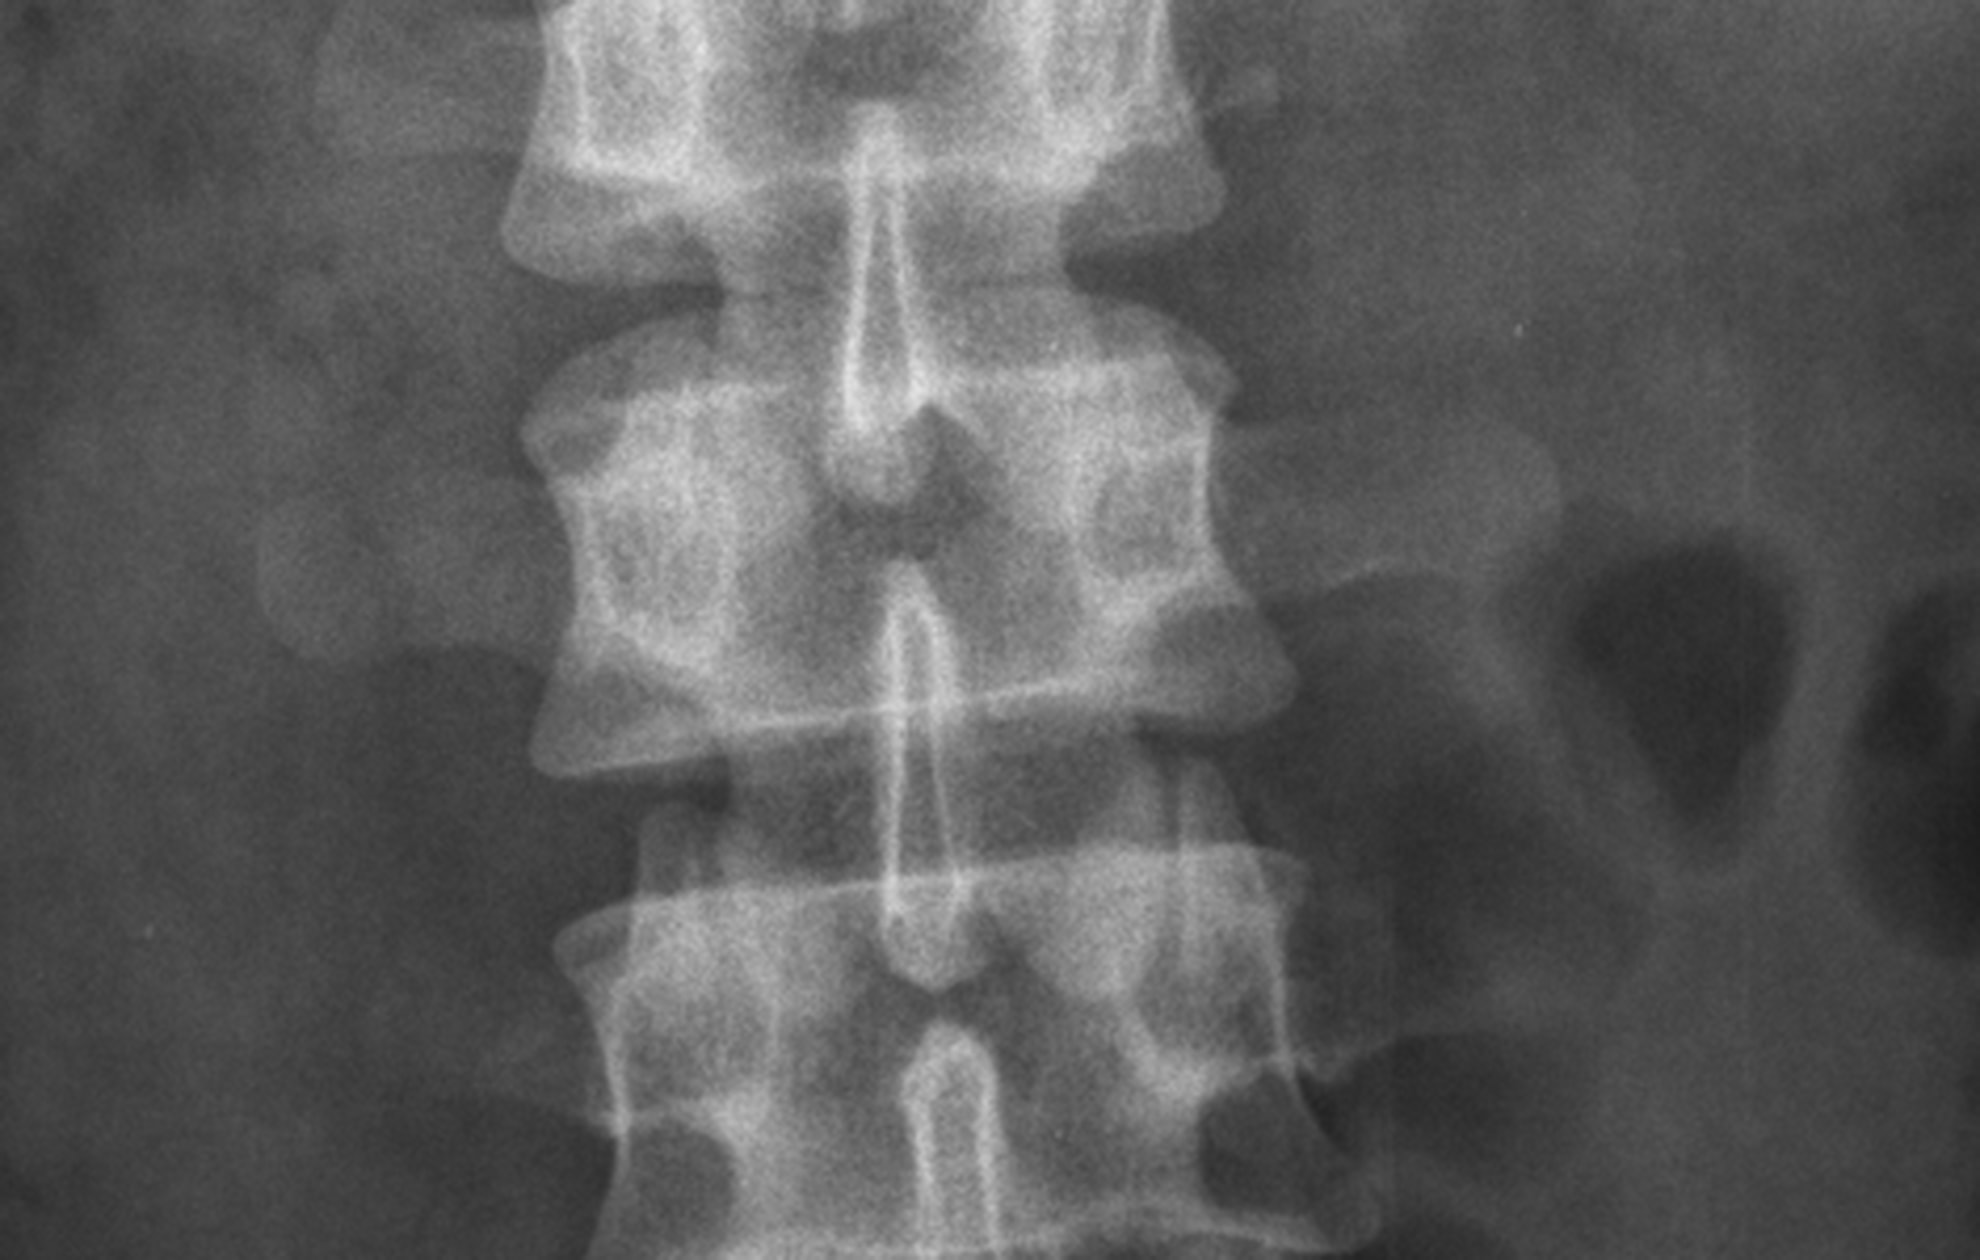

Bo får sit første rygsammenfald efter et løft. Nummer to får han til et firmaarrangement, hvor han deltager i sækkehop. Bo når kun at tage 3-4 hop, før han får en ubærlig smerte i ryggen. I 2011 får Bo sit tredje rygsammenfald, og nu insisterer han på at blive undersøgt. Hans stædighed bærer frugt, og DXA-skanningen på Gentofte Hospital viser svær knogleskørhed. Derudover har Bo tabt 8 cm i højden. Da han kommer tilbage til sin egen læge, undskylder lægen sig med, at Bo har sit køn imod sig.